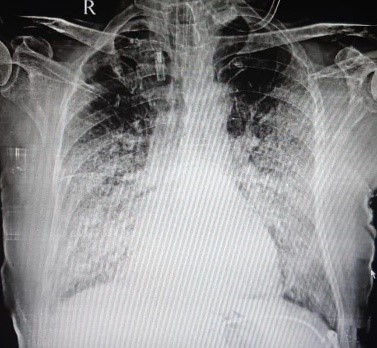

Mr M, 78 years was admitted under my care for the treatment of severe COVID 19. His oxygen level was very low on admission. If left unsupported, he would worsen dangerously. He needed high quantity of oxygen with special type of mask. His condition remained same for next two days. However on the evening of the third day I found him breathing rapidly. He complained that he spit blood in sputum so all forms of blood thinning medicines were stopped. Theses medicines are given to patients of severe COVID to prevent unwanted blood clotting. Late evening he complained of difficulty in breathing. On examination he was distressed. He was given non-invasive ventilator i.e. ventilator support with mask but he could tolerate it for few hours nothing was working for him. His condition deteriorated further with severe distress and mismatch with ventilator leading to fall in oxygen levels. I intubated i.e. inserted a tube in his wind pipe and kept him on ventilator. His X ray chest showed extensive shadows covering almost two third of the lung fields. COVID had badly affected his lungs and it was impossible for him to breathe on his own. He was managed with ventilator. His lungs were very stiff. For next three to four days he remained critical. However as the days passed his lung compliance improved. His X ray chest showed remarkable improvement. His ventilator support was reduced. He was given a challenge of self-breathing a day after his parameters improved. He did well and the tube that was kept in his wind pipe through his mouth for providing mechanical ventilator support was taken out. Now he was able to breathe on his own i.e. without any artificial support. His condition kept improving thereafter. He recovered well and discharged from the hospital

AFTER